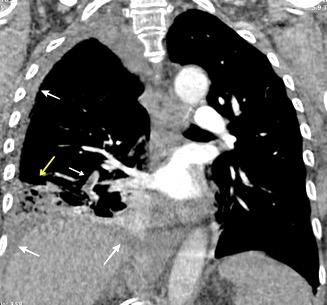

Tromboembolismo pulmonar.

Frecuencia del derrame:

Rx: 32%. TC: 47%

Unilateral. 85%

< 1/3 del hemitórax: 90%

Todos exudados

58% con eritrocitos

21% tabicación lo que causa demora en el diagnóstico

TEP. Empiema pleural. Atelectasia redonda

Porcel JM et al. Analysis of pleural effusions in acute pulmonary embolism: radiological and pleural fluid data from 230 patients. Respirology 2007/ Iguchi T et al. Desquamation of the subpleural lung parenchyma caused by empyema after pulmonary embolism: A case report. Respirol Case Rep. 2022 .